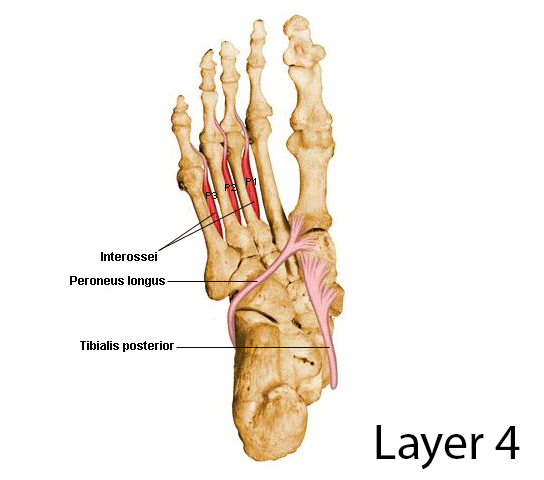

발의 생체역학 추가

1) 후족, 중족, 전족으로 힘의 분할을 나누는 법

2) 발의 2개로 세로 분할

중족골 1,2,3 metatarsal bone - 발가락 기준으로 50%, 25%, 25%의 부하가 주어짐.

3개 cuneiform

1개 navicular

- -> 관절면이 4개임. 관절면이 여러개 이므로 부드러운 움직임

중족골 4,5 metatarsal bone - 발가락 기준으로 50% 50%의 부하가 주어짐.

1개 calcaneus

1개 cuboid bone

- -> 관절면이 2개이므로 움직임이 덜하고 딱딱한 발.

보행시 추진력은 1,2지 발가락에 힘을 써서 걸어야 함. - 부하가 잘못되면 neuroma, 굳은 살 등이 생김

talus의 생체역학

- 근육이 부착하지 않는 유일한 뼈

- 3개의 축에 영향을 미침.